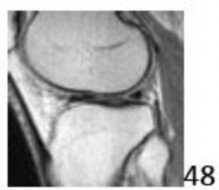

10. # An 18-year-old man sustains a twisting injury to the left knee while playing football. An MRI scan is shown in Figure 48. What is the most likely diagnosis?

1. # Anterior cruciate ligament rupture

DISCUSSION: The MRI scan shows a displaced, bucket-handle lateral meniscus tear. The sagittal view shows the typical

"large anterior horn" sign, or "double meniscus" sign in which the displaced bucket-handle fragment appears just anterior to the native anterior horn of the lateral meniscus. The presence of the fibula on the sagittal view confirms this as the lateral compartment. The image is lateral and the cruciate ligaments are not visualized. The articular cartilage shown does not demonstrate an osteochondral lesion Preferred Response # 48 is 4.